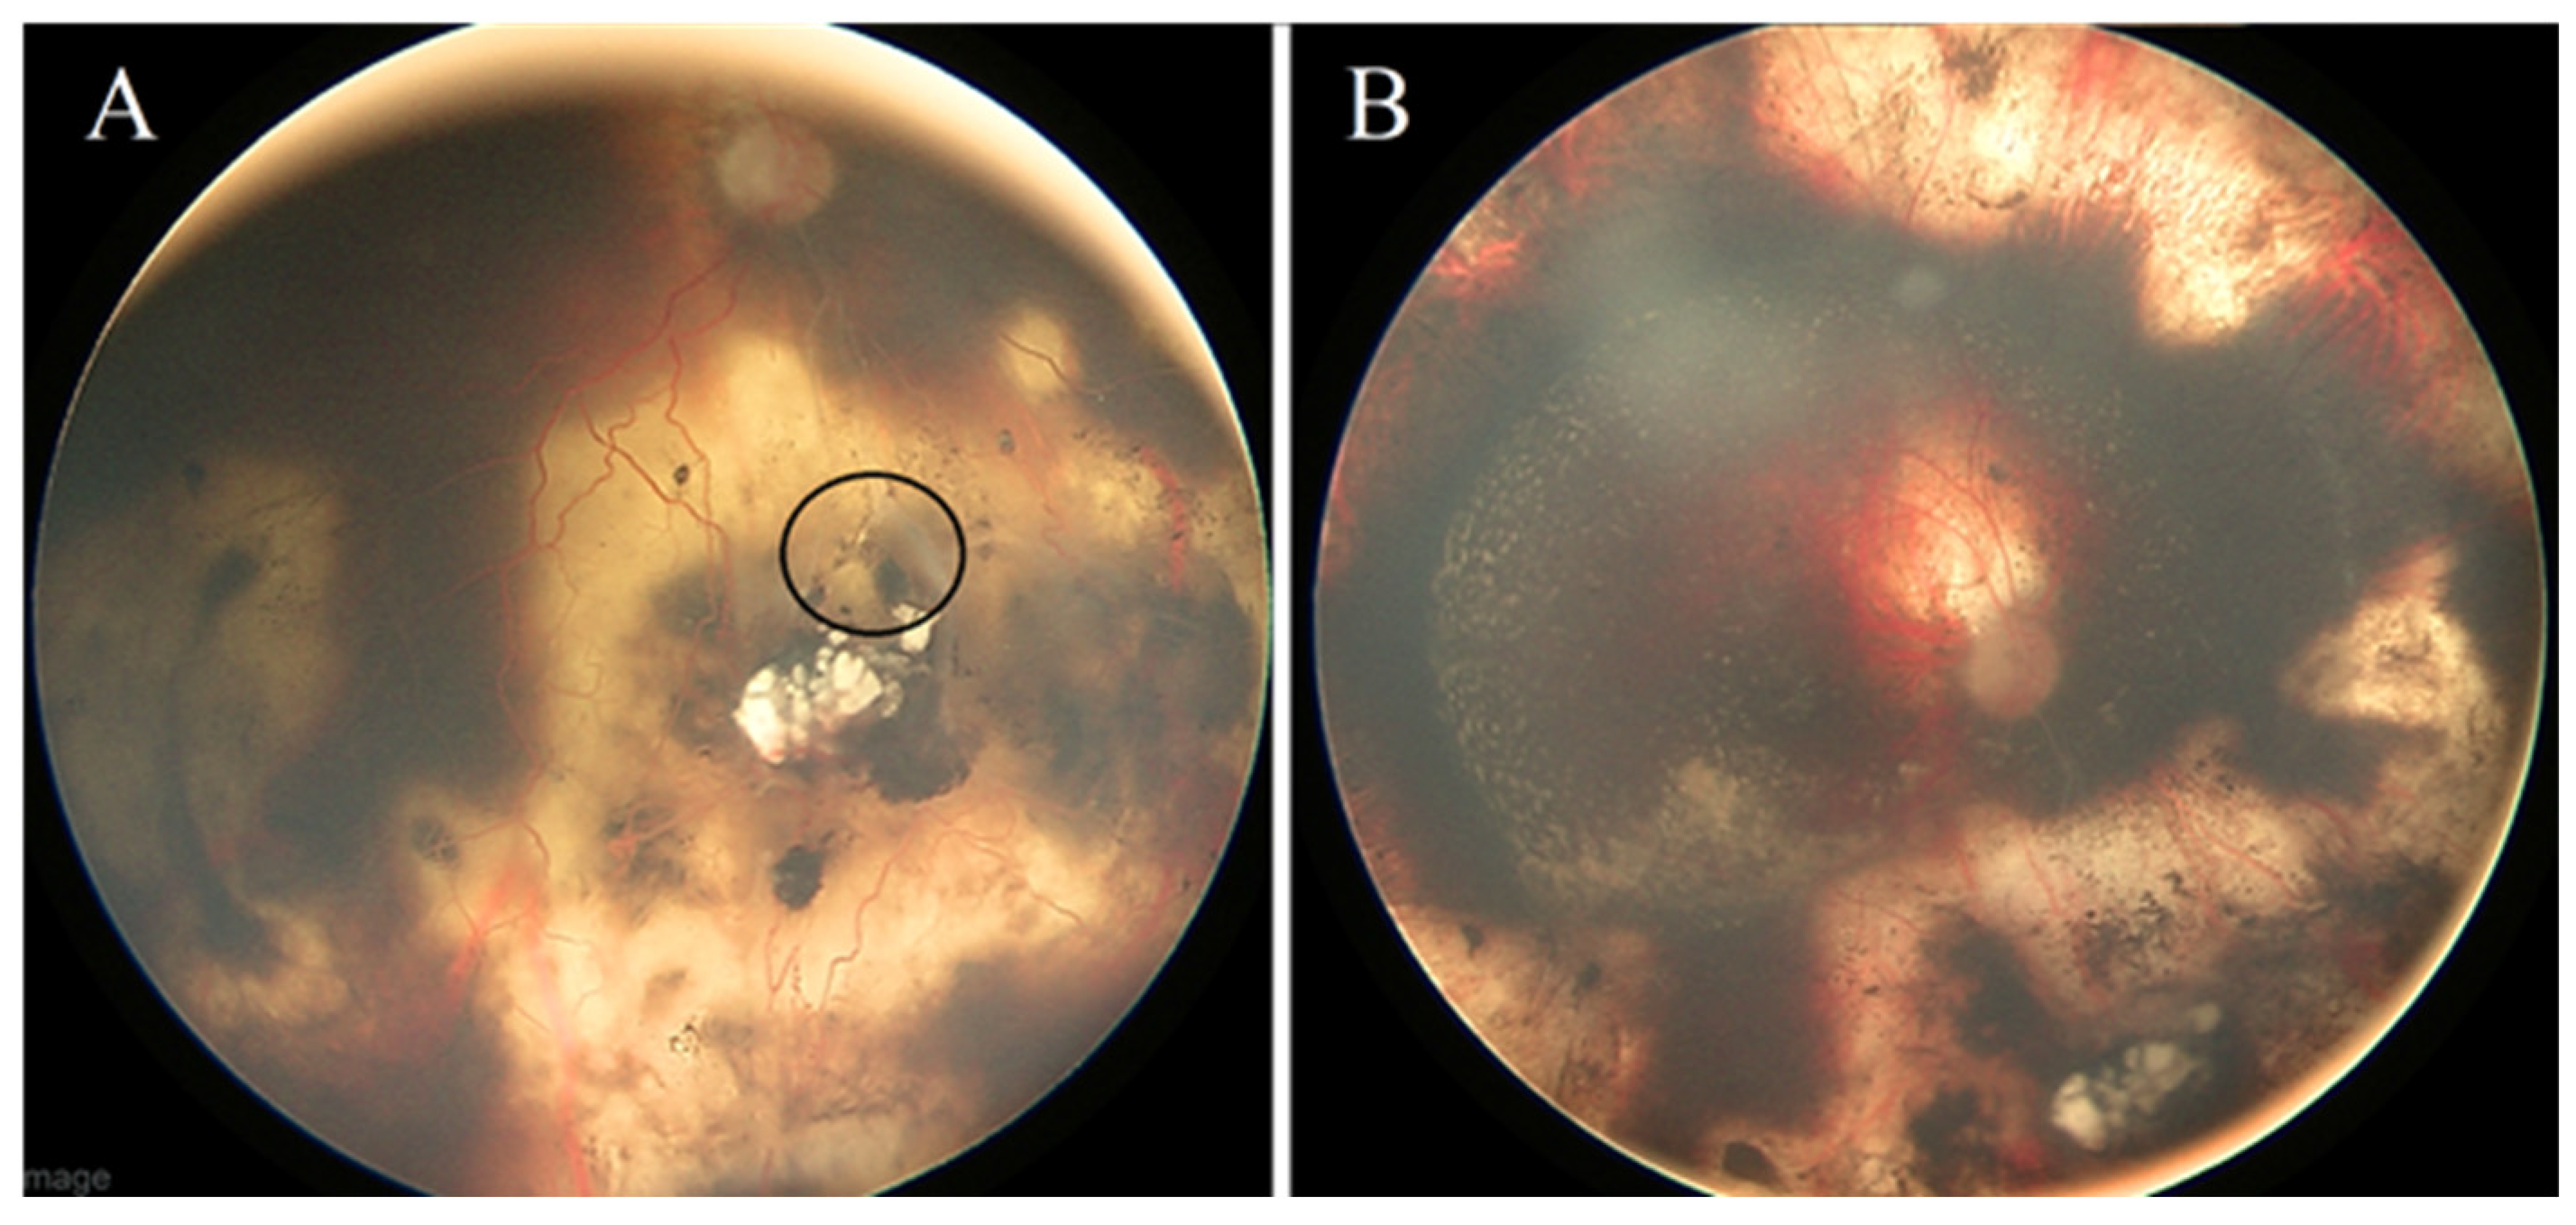

Case #5: A 4-year-old male patient was diagnosed with unilateral Rb in the right eye (classified as ICRB group D). His treatment involved systemic chemotherapy (comprising eight cycles of CVE) combined with focal consolidation therapies (laser and cryotherapy). Additionally, the right eye received multiple intravitreal Melphalan injections to address active vitreous seeds. The tumor exhibited an excellent response to the aforementioned treatments. However, during a subsequent follow-up examination, the patient developed RRD (

Figure 4A), which required scleral buckling with no need for fluid drainage. A follow-up eye exam 14 months later revealed that the retina remained attached with no indications of new tumor activity (

Figure 4B).

Case #6: A 16-month-old female patient was diagnosed with bilateral Rb (ICRB group D for both eyes). Initially, her treatment plan involved systemic chemotherapy and focal consolidation therapy. However, she later developed RRD in the left eye (

Figure 5A), necessitating a scleral buckle procedure without fluid drainage. At her subsequent follow-up visit after three weeks, the left eye showed substantial retina reattachment. Throughout her follow-up appointments, she underwent multiple argon and TTT treatment sessions to address signs of tumor activity. Unfortunately, her right eye exhibited extensive recurrence involving retinal tumors and vitreous seeds. In response, intra-arterial Melphalan chemotherapy was initiated for her right eye, but regrettably, it did not yield a favorable response. After four weeks, the decision was made to proceed with enucleation of the right eye. At her most recent follow-up, conducted 15 months after the scleral buckle surgery, the retina remained flat and securely attached, with stable and inactive retinal tumors (

Figure 5C).